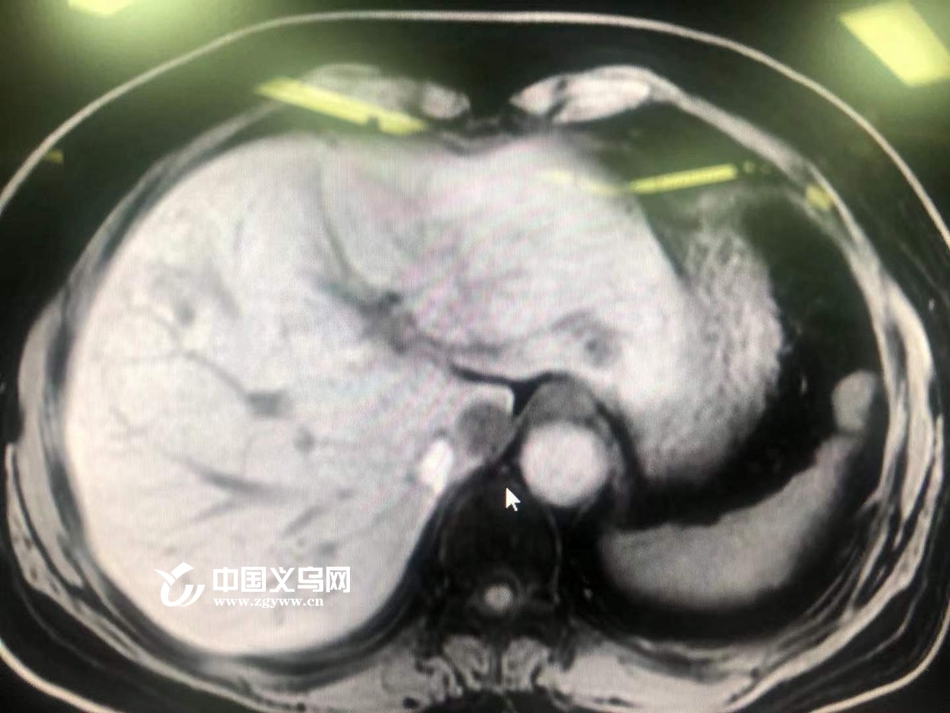

患者吴阿姨,今年55岁,来自宁波,曾先后接受过肝脏肿瘤切除手术和肝脏肿瘤消融手术。前段时间,肝脏肿瘤再次复发且位置非常危险,与两根血管距离不到1毫米,并且肿瘤上下方还有2根静脉距离不足2毫米。

“基本是紧贴着,相当于是压迫了。这两支血管如果在手术中破裂,基本5分钟后人就没有了。”浙大四院普外科唐喆教授说,这种情况通过可以纳米刀技术来消灭肿瘤。

据介绍,纳米刀对血管和神经没有损害,唯一的困难是要在这么危险的位置放置两根电极,对术者的技术要求相当高。唐喆教授于2009年在英国进修学习时熟悉掌握纳米刀技术,2015年在杭州开展省内第一例纳米刀肝脏肿瘤消融手术。目前浙大四院引进了纳米刀设备,唐喆将为吴阿姨开展浙中第一例肝肿瘤纳米刀(不可逆电穿孔)手术。